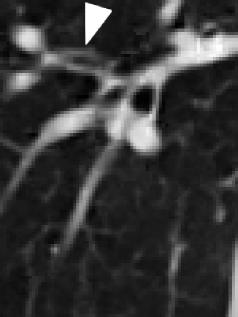

(a) original slice (b) original transform (c) mesh-based compensation (d) block-based compensation

(blurred) (sharp) (more details)

For visual comparison of the lowpass bands of the different approaches, a zoom into one slice of the lowpass band of thorax2 is shown in Figure 2. Compared to the corresponding original slice in Figure 2 (a) the blurriness of the lowpass band of the original transform can be seen in Figure 2 (b). The lowpass bands of the compensated transforms in Figure 2 (c) and (d) represent the structures sharper and more detailed.